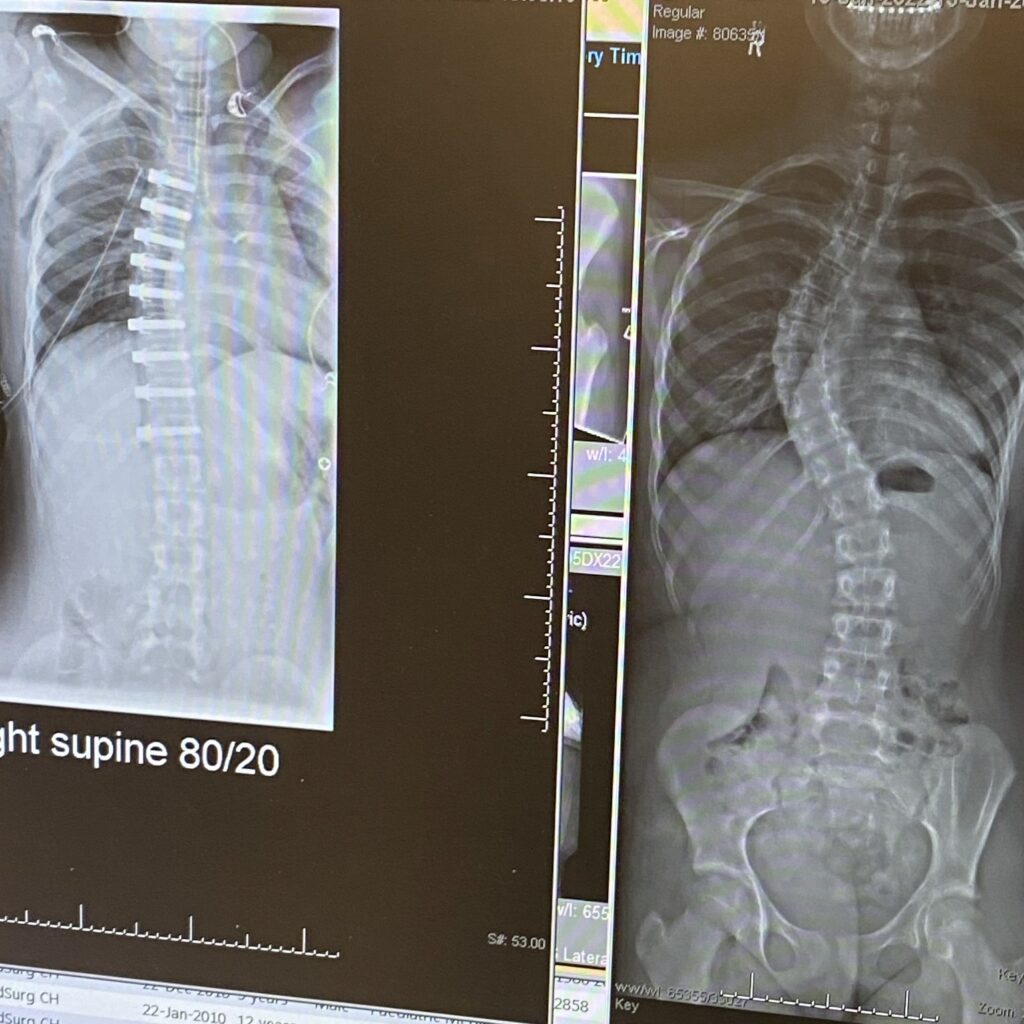

At my follow-up appointment, I learned I had a 54-degree curve and needed emergency surgery. I was in the perfect time bracket in my puberty growth, and I was eligible for the VBT surgery. That same day, I also received the news that my surgery was happening in two weeks. In a way, I believe the speed of the pre-surgery process helped me a lot, as I didn’t have much time to anticipate what was going to happen to me. Nevertheless, I was still very worried about the surgery. Eventually, the day of my surgery came: January 26th, 2022. As you can imagine, I was scared out of my mind. But I stuck it out and did it! The surgery was successful, bringing my curve to 24 degrees, down from 54 degrees.